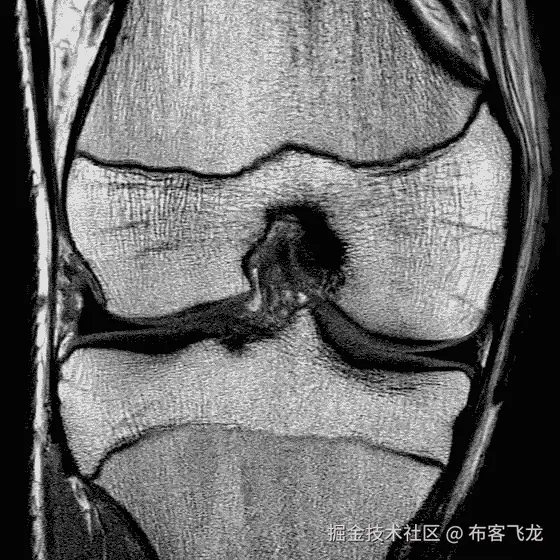

使用 3D 膝关节磁共振成像和卷积神经网络进行年龄评估

One of the 145 samples that was part of the data set

你能猜到这个膝盖核磁共振后面的人有多大年纪吗?我给你一个提示。这是一个 14 到 21 岁的德国男性的录音。不知道吗?我喜欢想象这是神经网络在被训练之前看待世界的方式。它完全没有线索。所以,让我来训练你。

作为德国研究基金会(DFG)的一项研究的一部分,我接触了一组 3D 核磁共振成像数据,显示了德国男性的右膝盖。图像上半部分的股骨是大腿骨,正下方的胫骨是胫骨。在录像的后面,你可以看到另一块骨头在左下角冒出来——腓骨。如果你看得更近,你可以在骨头上发现几乎像裂缝一样的黑色水平线。这些被称为生长板,因为这是你的骨骼实现纵向生长的地方。它们由软骨组成,这就是为什么它们可以在核磁共振成像记录中看到。一旦你停止生长,这些区域会慢慢地开始闭合,直到看不见为止。

Examples of a 14, 17 and 20 year old caucasian male (left to right)

我们在这项研究中使用了膝盖记录,因为我们知道可见的生长板在成年前会关闭。其他研究使用核磁共振成像或手部 x 光,已知手部生长板关闭较早。在上面的图片中,你可以看到黑色水平间隙的宽度是如何与一个人的年龄相关的。